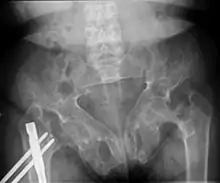

Brown tumors in the pelvis and a hip fracture.[17]

Subchondral resorption in the sacroiliac joint.[17]